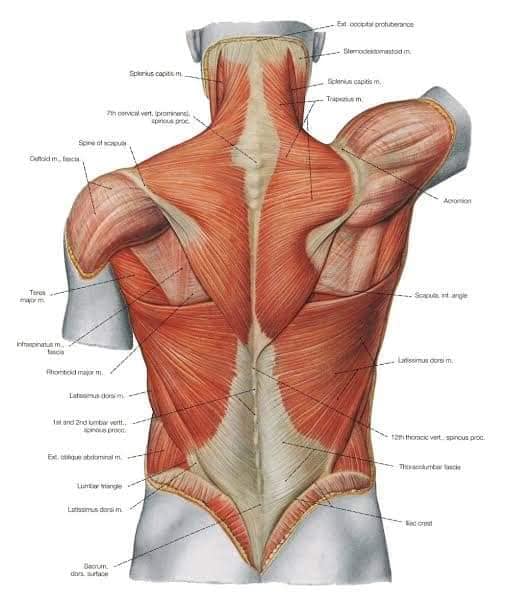

Спинні м'язи

Спинні м'язи виконують функції підтримки хребта, а також дозволяють здійснювати рухи тулуба.

Поверхневі спинні м'язи

М'язи, що піднімають лопатку: Трапецієподібний м'яз: великий м'яз, що покриває верхню частину спини. Його функція - підтримка і рух лопаток, а також забезпечення стабільності хребта.

М'язи, що ведуть лопатку до хребта: Широкий м'яз спини: великий м'яз, що розташований в нижній частині спини. Він відповідає за рухи плечей і лопаток, а також за розширення верхньої частини тулуба.

Глибинні спинні м'язи

М'язи, що забезпечують стабільність хребта: М'язи, що розташовані між хребцями: включають мускулатуру, яка забезпечує стабільність і підтримку хребта, а також дозволяє здійснювати рухи хребта.

М'язи, що здійснюють ротацію та нахили

М'язи, що забезпечують ротацію хребта: Ротаційні м'язи: допомагають у здійсненні обертальних рухів тулуба, а також у підтримці рівноваги і стабільності хребта.